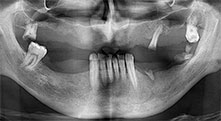

Your hospital in Timisoara offers oral surgery and prosthetic reconstruction with a concentration on implantology. Do you also use your Piezomed device for other indications?

Bratu: We also use piezo for surgical crown extensions and in periodontal surgery.